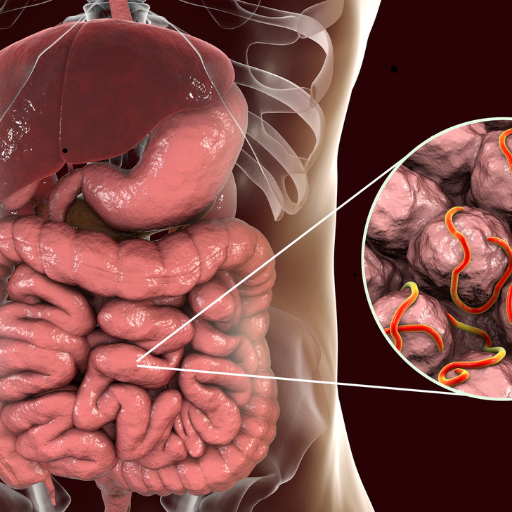

Gastrology